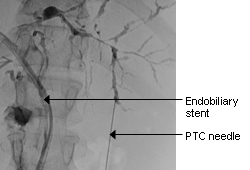

Typical endoscopic retrograde cholangiopancreatography findings in a patient with PSC: multi-focal strictures of the intra- and extrahepatic bile ducts

Dr Kris Kowdley's collection